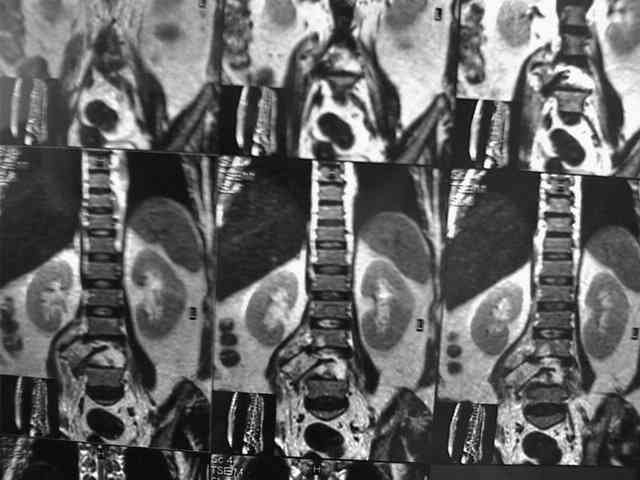

Женщина получила травму более 1 мес назад, когда оказалась под колесами крытого пикапа (мы его раньше называли "пирожковозом"). Причем машина сдавала назад, ехала не быстро и упав, женщина оказалась под тяжестью кузова и заднего моста машины. Так она пролежала, пока водитель не обнаружил ее там, а затем не позвал на помощь людей, которые машину приподымали...

При этой картине удивительно еще то, что у нее нет никаких двигательных и тазовых нарушей.. Жалобы только на боли в спине. Движения и чувствительность в полном объеме. Никаких повреждений сосудистых магистралей также нет. Только изолированный перелом L5 со смещением тела позвонка в мягих тканях (забрюшинном пространстве). Остистый отросток на месте.

В приложении - МРТ.